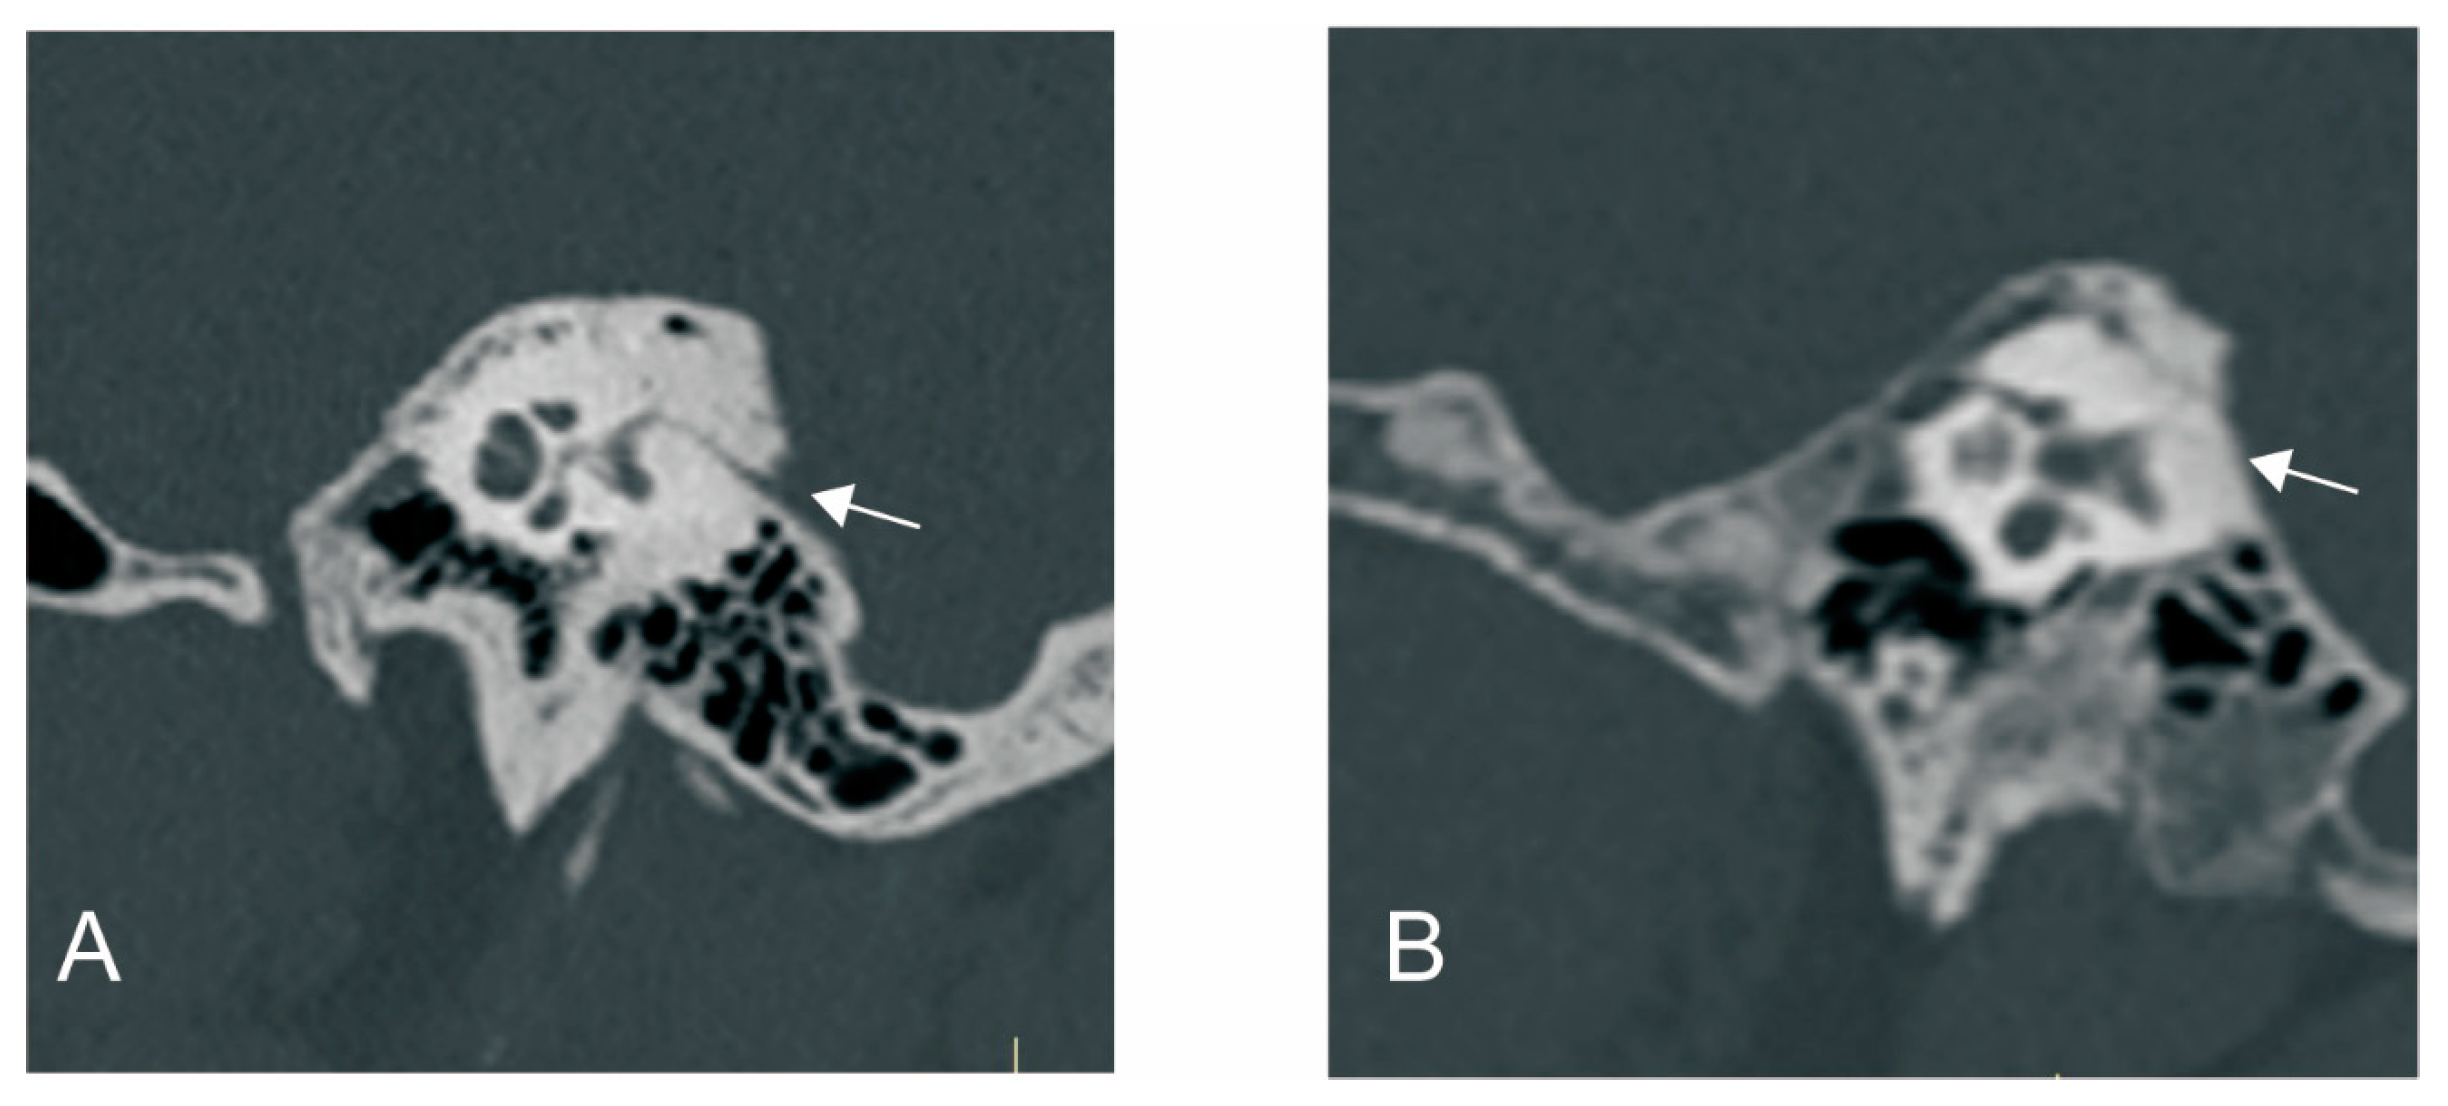

3.2.1. The Relationship between ATVA and VA Visibility and Morphology

2.2.2. Radiological Measurement